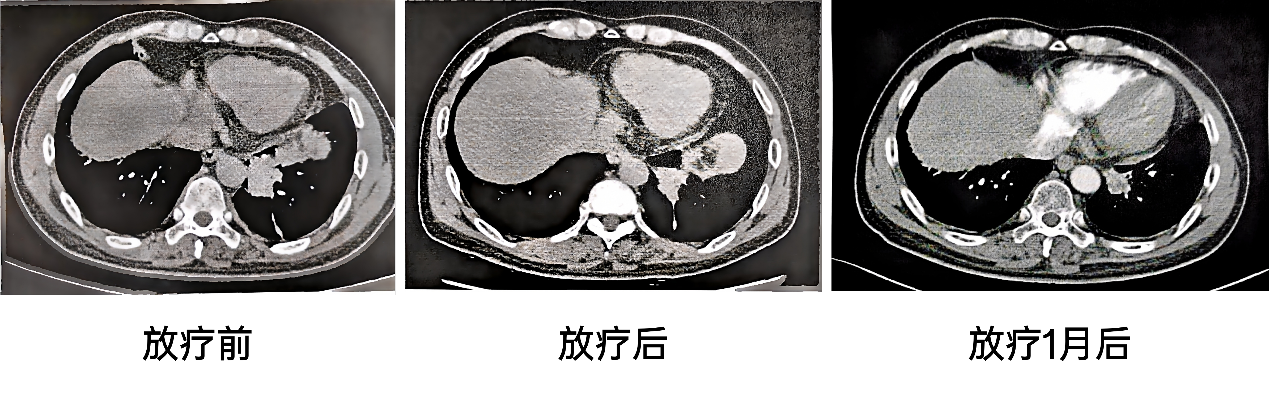

2025-4-14胸部CT(放疗末):肺结节消融术后,左肺下叶软组织肿物伴周围肺组织膨胀不全,较前(2024-12-25)缩小;纵隔多发淋巴结,较前片缩小。

2025-5-19胸部CT(放疗后1月):肺结节消融术后,左肺下叶软组织肿物伴周围肺组织膨胀不全,较前(2025-4-14)变化不大;纵隔多发淋巴结,较前片变化不大。